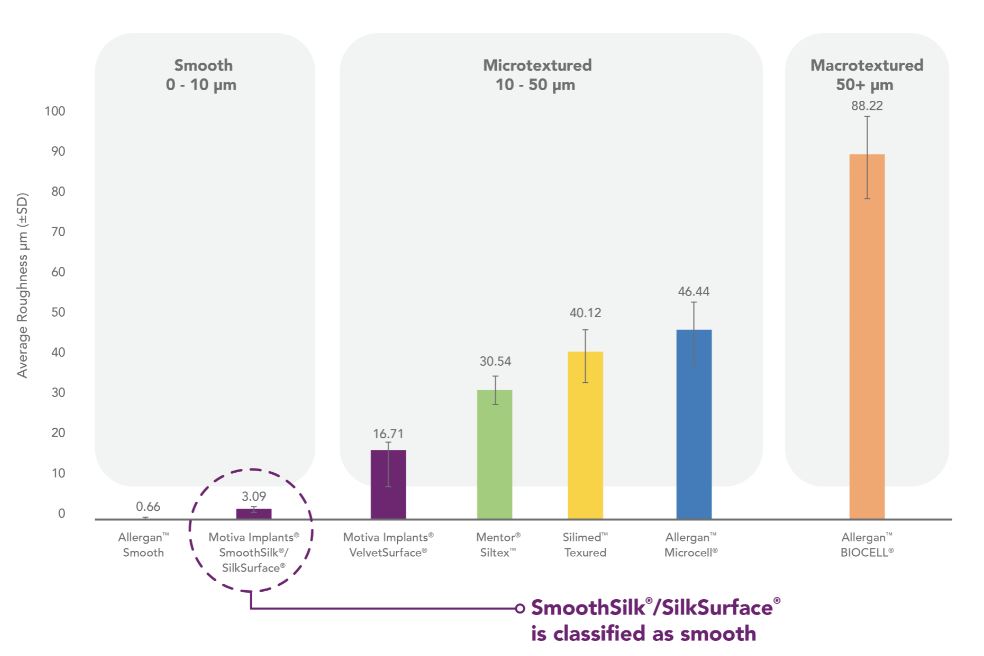

SilkSurface/SmoothSilk

The International Standard Organization, or ISO, through the new April 2018 standard (ISO 14607:2018), created a classification of implant surface textures according to roughness. This standard includes an objective way of defining the difference between smooth, micro and macro surfaces based on roughness average. The topology of SilkSurface/SmoothSilk is characterized under the smooth category, having a low roughness value of 3.09 microns with thousands of contact features per square centimeter.

Our retrospective implant data shows that Motiva Implants have a lower rate of capsular contracture and seromas when compared to available published data from competitors. We believe that these results are due in large part to the proprietary surface of our Motiva Implants. Our proprietary shell surfaces are smoother and have more regular surface features than those of our primary competitors based on several studies using methods such as scanning electron microscopy, profilometry testing and statistical parameters comparisons.

A study performed in mice at the Langer Lab, by Professor Robert Langer, Institute Professor at the Massachusetts Institute of Technology, or MIT, Department of Chemical Engineering indicated that our SmoothSilk/SilkSurface attracts fewer macrophages than a traditional smooth surface. A larger percentage of macrophages in the cell mix indicates an inflammatory response, which is an early step in capsule formation. We believe the more moderate inflammatory response observed on SmoothSilk/SilkSurface is responsible for improved biocompatibility and lower complication rates.

In addition, an abstract presented in 2017 by researchers at Montana State University showed less accumulation of both bacteria and biofilm on SmoothSilk/SilkSurface in vitro when compared to smoother and textured surfaces. Biofilm formed on implant surfaces increases the risk of bacteria accumulation and capsule formation.

In December 2018, we commissioned a report from the French reference laboratory Laboratoire National de Metrologie et d’Essais, or LNE, on the mechanical characteristics of our Motiva implants. Based upon its testing, LNE concluded that the SmoothSilk/SilkSurface shell surface in the Motiva implants is considered a smooth surface as defined by ISO 14607:2018 categorization.

The graph below shows how the size of our surface features compares with those of our competitors.